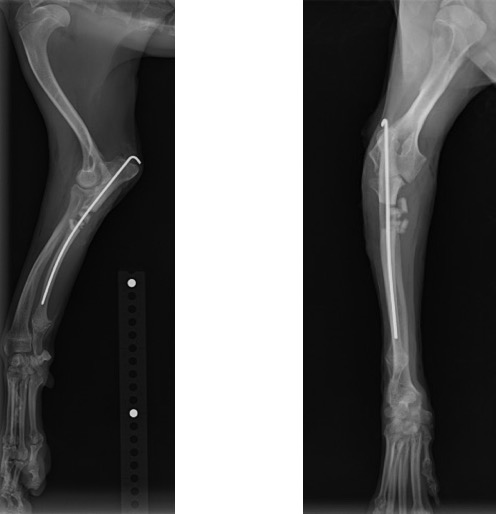

術後のLateral像とAP像 (前例と同じく髄内ピンとしてK-wireを刺入したのちに切り取った骨片を破砕し、骨切部分へ再移植しました。)

術後1ヵ月 (移植した骨が少しずつ癒合し始めてきましたが、K-wireの先端が軟部組織を刺激してしまっているためか、肘頭の腫脹が認められました。)

術後2ヵ月 (K-wireの先端が軟部組織を刺激し、患肢の着地を阻害していると考えられたため、抜ピンを実施しました。)

術後3ヵ月 (移植骨の癒合良好で、K-wireの刺入孔も不明瞭化してきました。)

術後6ヵ月 (骨切り線が完全に消失しました。)